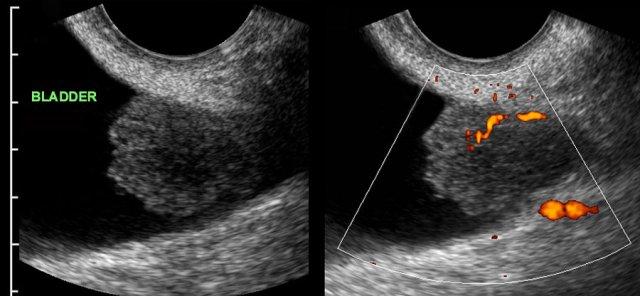

DIE tại trực tràng

Các hình ảnh thuộc về một bệnh nhân DIE với hình thái tử cung và buồng trứng bình thường.

DIE có các đặc điểm TVUS điển hình, gần như đặc trưng bệnh lý.

Mặc dù rõ ràng là một bệnh lý phụ khoa, nhưng không hiếm trường hợp bị các bác sĩ phụ khoa bỏ sót trong quá trình thực hiện TVUS.

Lý do là phần lớn bệnh nhân DIE (*) không có các nang lạc nội mạc tử cung điển hình và, như ở bệnh nhân này, có tử cung và buồng trứng bình thường (buồng trứng trái và buồng trứng phải). Hơn nữa, chẩn đoán TVUS của DIE đòi hỏi kiến thức chuyên sâu về hình ảnh siêu âm của ruột và bàng quang bình thường cũng như bệnh lý, kiến thức này có thể còn thiếu ở các bác sĩ phụ khoa.